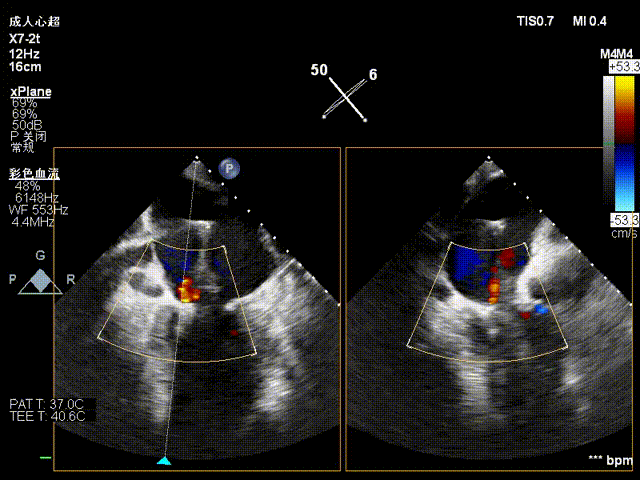

夹合后反流评估

检查示组织桥明显,夹合器稳定,残余反流明显减少,降低至1+等级,二尖瓣平均跨瓣压差为2mmHg,经团队评估,手术效果达既定预期,各项指标平稳,顺利结束手术。